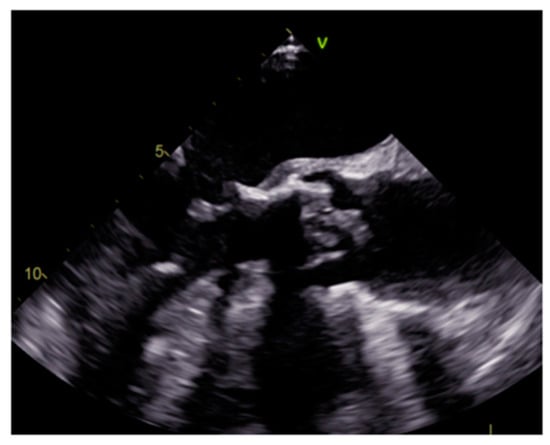

4.2. Papillary Fibroelastoma (PFE)

| Papillary fibroelastoma | Adulthood | Valves | Usually, asymptomatic. Rarely embolic events | Atrial side of the mitral valve or the aortic surface of the aortic valve leaflet | Stippling and vibration or shimmer of the peripheral edge. | Hypodense, smooth, peduncolated, attached to the valve leaflet by a short pedicle | Iso T1w, Hyper T2w, hypo cine with surrounding turbolent flow, poor LGE |